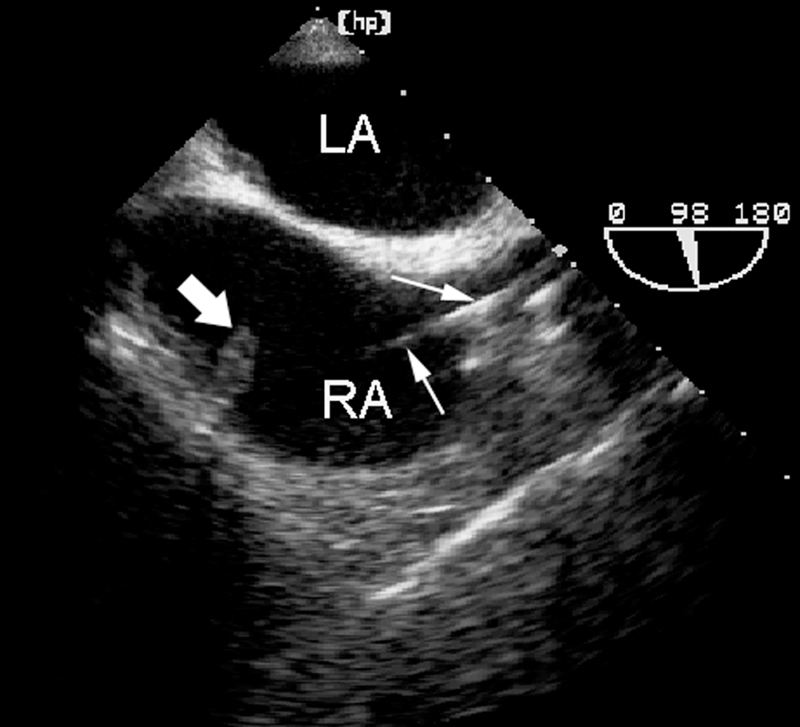

فحوصات تشخيصية لبعض امراض القلب والشرايين التاجية